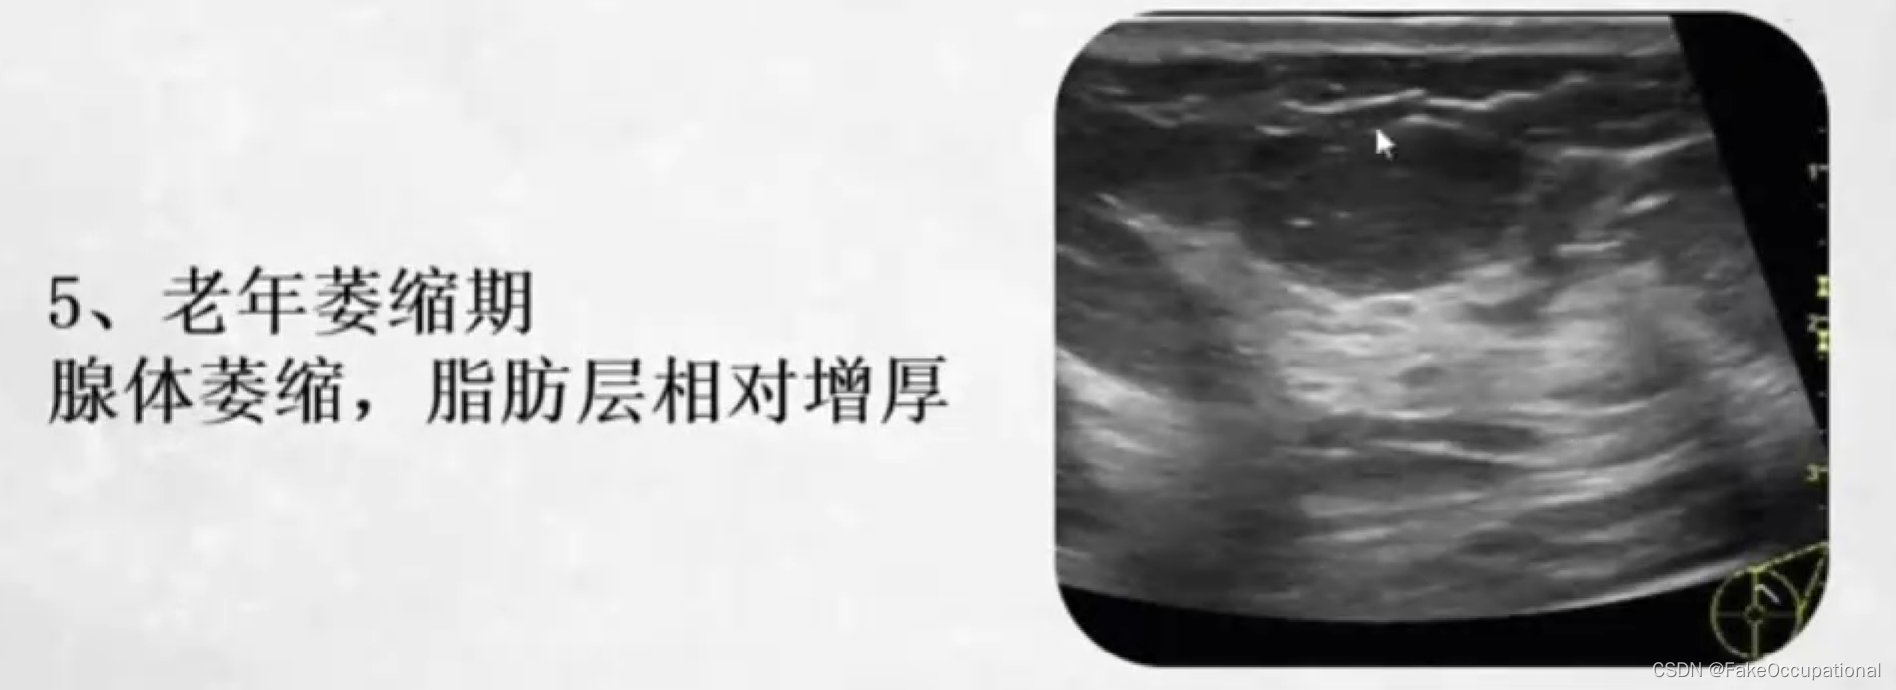

正常乳腺超声表现

- 高回声的皮肤层,低回声的皮下脂肪层